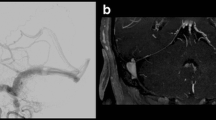

Individual CTA and MRI/MRA imaging signs were recorded as positive or negative. The CTA signs of CVR included abnormal dilatation, early enhancement, and the presence of a medullary or pial vein [6]. The MRI/MRA signs of CVR included abnormal dilation, flow-related enhancement, clustered of flow void, early enhancement, and presence of a medullary or pial vein [11, 12]. Individual CTA and MRI/MRA signs with corresponding catheter angiography are shown in Fig. 1. The above signs comprised the grading system for CVR. If a discrepancy occurred between the two readers, the findings were discussed until a consensus was reached. The grading systems for CTA and MRI/MRA were used to consider the trade-off between sensitivity and specificity, as well as the correlation between different signs. Details of the grading systems are shown in Table 4.

a–h A 31-year-old man with left transverse-sigmoid sinus DAVF was presented with seizure. a Axial CT angiography demonstrates dilated cortical venous pouch (white arrow). Early enhancement is revealed as compared with the adjacent dural sinuses. b Sagittal view of CTA shows dilated medullary veins in the occipital lobe (black arrows). c Reformatting CT angiography clearly depicts the venous pouch and its drainage (white arrow). d Axial T2-weighted image shows the dilated structure (white arrow) with dark signal, suggestive of flow void in the venous structure. e Axial time-of-fight image reveals the flow-related signal in the venous pouch (white arrow). f Coronal contrast-enhanced MR angiography demonstrates there is early, intense, enhancement in the venous structure as compared with adjacent dural sinus (white arrow). g Sagittal T1-weighted post-contrast image shows the dilated medullary vein the occipital lobe as well (black arrows). h Angiography confirms the Cognard type IV DAVF with direct drainage into ectatic cortical veins (black arrows). The image is corresponding to the reformatting CTA nicely